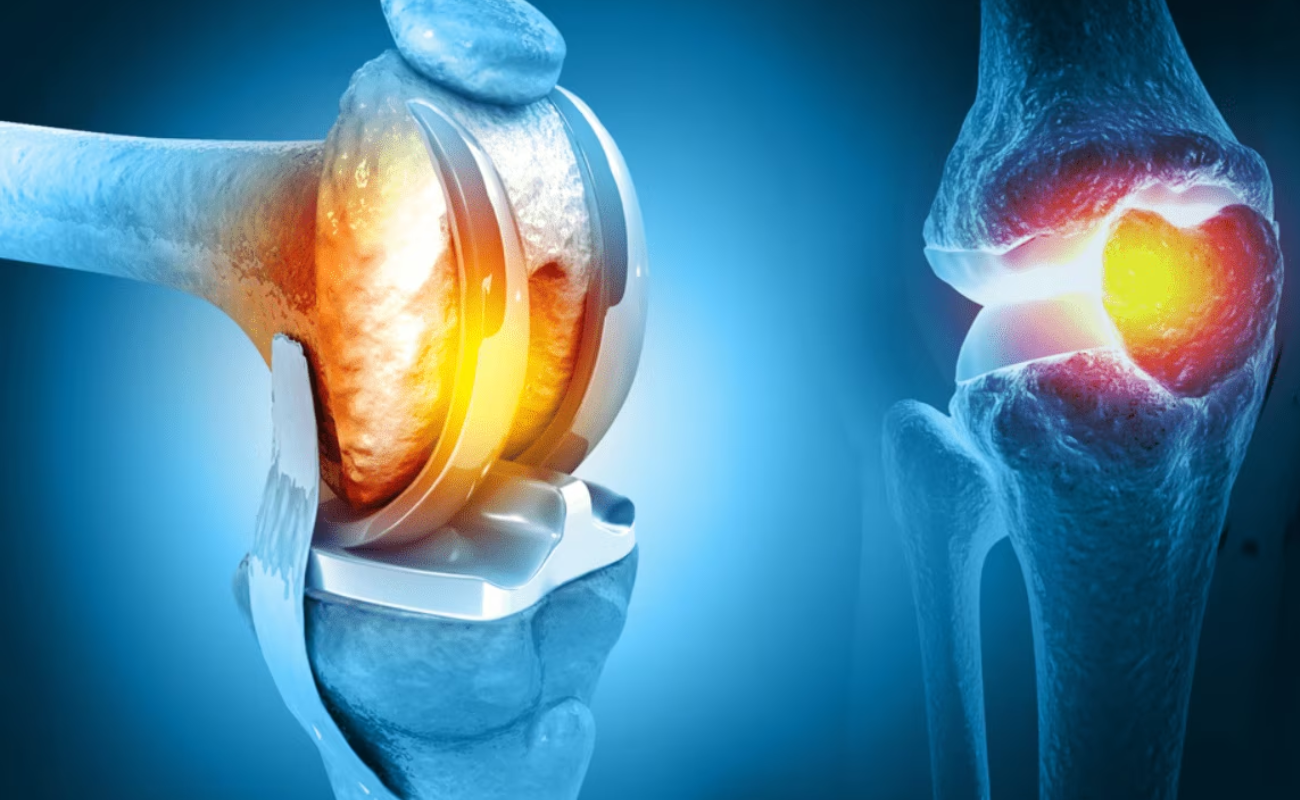

Osteoarthritis

Osteoarthritis leads to loss of cartilage when rate of cartilage damage exceeds the rate of repair. Cartilage is necessary to prevent bones from rubbing against each other. When the cartilage cover is lost, the bones come into contact and result in painful movement.

Articular Cartilage Damage

Articular Cartilage is the layer of smooth connective tissue that covers the ends of bones at every joint. This tissue is maintained and repaired on a continuous basis. It is one of the most lubricated materials on earth and has the lowest coefficient of friction,

10 Signs That You Could Require Knee Replacement Surgery

Knee replacement surgery is a common surgical procedure that is performed to alleviate knee pain and improve mobility. However, it is a major surgery that should only be considered after all other treatment

Knee Replacement Surgery: When Is It Time?

Knee pain and mobility issues can significantly impact a person's quality of life. When conservative treatments fail to provide relief and daily activities become increasingly challenging, knee replacement surgery may be considered.

The Benefits of Robotic Knee Replacement Surgery

In recent years, medical technology advancements have brought about a revolution in the field of orthopedic surgery, particularly in the realm of knee replacements.

The Impact of Robotics on Knee Replacement: Revolutionizing Orthopedic Surgery

In recent years, orthopedic surgery has undergone a revolutionary transformation through the integration of robotics in knee replacement procedures.